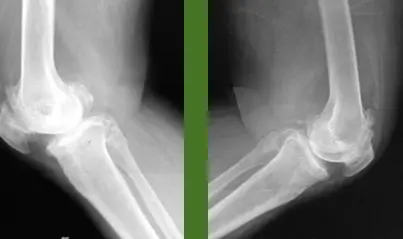

Injection for Tennis elbow (Lateral Epicondylitis)

This patient has lateral epicondylitis. You are required to give him an injection

![]() |